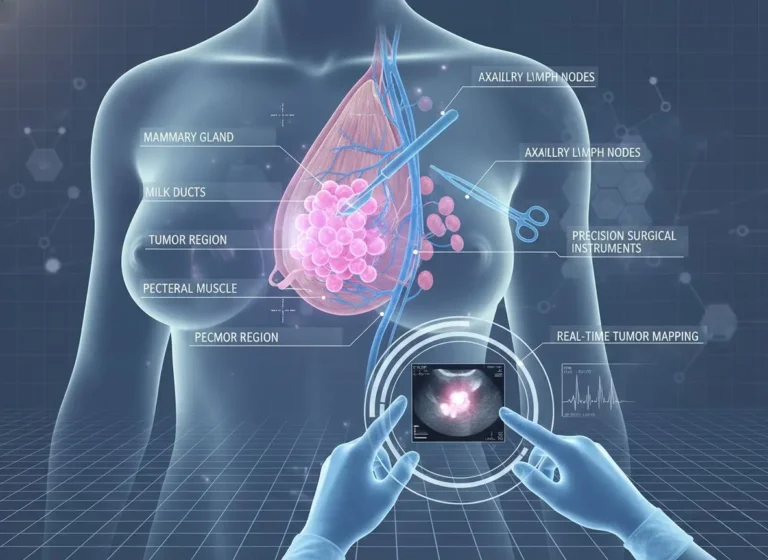

Essentials Advanced Breast cancer treatment in Mira Road. Breast cancer remains one of the most pressing health challenges worldwide, and surgical intervention…

Introduction Minimally Invasive Cancer Surgery in Mira Road. Let’s understand, Cancer treatment has evolved dramatically over the past few decades, with surgical…

Introduction Hearing the words breast cancer can feel overwhelming. If you’re here, you or someone close to you might be facing difficult decisions. One…

If you or someone you love is facing breast cancer, the idea of surgery can feel overwhelming. In this guide, we’ll walk…